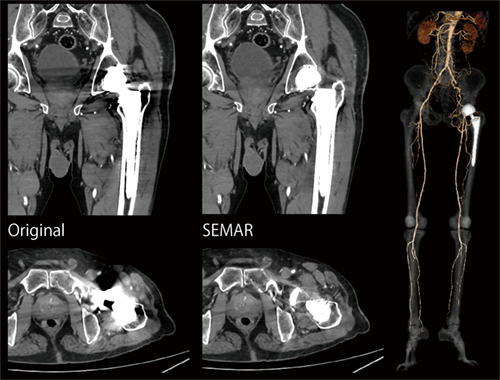

症例2 下肢動脈造影(SEMAR適用)

腎機能低下(eGFR 40mL/min/1.73m2)のため、造影剤低減プロトコール(2割低減)にて撮影。人工股関節による金属アーチファクトをSEMARにて効果的に低減。

Aquilion Serveの導入後、CT検査は月間約160件と以前に比べて1割程度増加している。村上放射線科部長は、「画質の向上と低被ばくで検査が可能になったことで、依頼件数が増加しています」と言う。Aquilion ServeではAiCE-iによって被ばく線量が低減されており、冠動脈や胸部でDRLs2020の半分、腹部や胸腹部では1〜2割減で検査を行っている。また、下肢動脈造影検査では、撮影スピードの向上によって広範囲を短時間で撮影できることから、造影剤量を従来の2〜3割程度削減できた。さらにAquilion Serveでは、金属アーチファクト低減技術の「SEMAR(Single Energy Metal Artifact Reduction)」も利用できる。SEMARの運用について村上放射線科部長は、「人工骨頭のアーチファクトが除去されて下肢動脈が明瞭に描出され、診断が可能な画像が提供できています」と述べる。